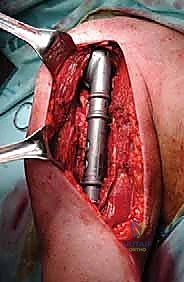

* يتم فتح شق جراحي، وعزل الأعصاب (خاصة العصب الكعبري).

* يتم تجريف الورم بالكامل (Curettage) للوصول إلى أنسجة عظمية سليمة.

* يتم استخدام مثقاب عالي السرعة لإزالة أي خلايا سرطانية متبقية، وقد تُستخدم مواد كيميائية (مثل الفينول) أو الكي الحراري لقتل الخلايا المجهرية.

* يُملأ الفراغ العظمي الكبير بـ الإسمنت العظمي الطبي (Polymethylmethacrylate - PMMA). هذا الإسمنت لا يعوض العظم المفقود فحسب، بل إن الحرارة العالية التي يولدها أثناء تصلبه تقتل أي خلايا سرطانية متبقية.

* يتم تدعيم البناء بشريحة معدنية طويلة ومسامير قوية لضمان الاستقرار الميكانيكي.

العزل العصبي الوعائي: هذه هي الخطوة الأهم. باستخدام أدوات الجراحة الميكروسكوبية ونظارات التكبير (Loupes)، يتم تحديد وعزل الأعصاب والأوعية الدموية وحمايتها بأشرطة ملونة.

استئصال الورم: يتم قص العظم بمنشار جراحي دقيق أعلى وأسفل الورم بمسافة أمان (Margin)، ويتم استخراج الكتلة الورمية بالكامل وإرسالها لمختبر الباثولوجي.

إعادة البناء الميكانيكي: يتم إدخال المكونات المعدنية (سواء مسمار نخاعي، شرائح، أو مفصل صناعي) وتثبيتها بقوة باستخدام الإسمنت العظمي إذا لزم الأمر. يتم التأكد من ثبات الهيكل الجديد تحت جهاز الأشعة السينية المباشر (C-arm).